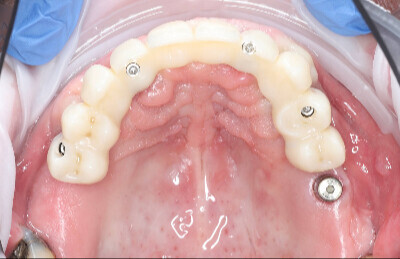

Navigovaná chirurgia, 5 implantátov

Autor práce Dr. Michal Repaši

Zubný technik Vasil Csopej

22. september 2021